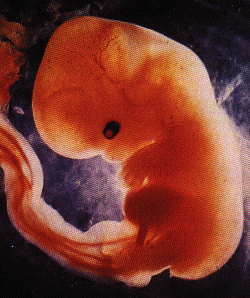

10 – 12 haftalık fetus

Anne karnında 12 haftalık bebeğin 3d görünümü.jpg